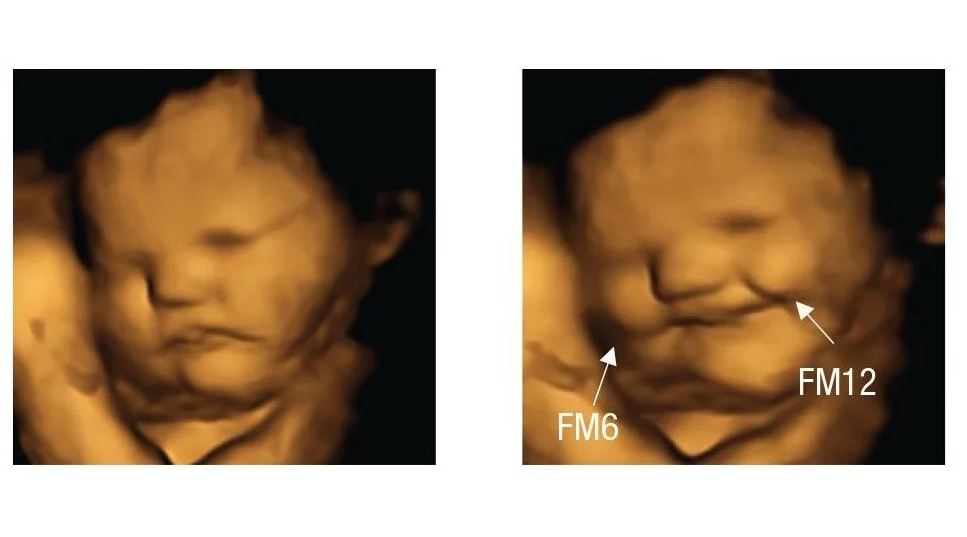

Si el sabor de la col rizada te hace fruncir el ceño, no estás sola.…